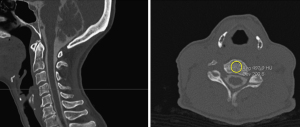

HU measurements were performed on preoperative sagittal cervical CT scans using standard bone windows. For the primary analysis, operative-level HU was defined as the mean trabecular HU of the two vertebral bodies adjacent to the index disc space (i.e., cephalad and caudal vertebrae forming the operative level), reflecting the local bone quality most relevant to cage subsidence. HU values at non-operative cervical levels (C2–C7) were collected only for secondary descriptive and exploratory analyses and were not used for primary inferential modeling. For each vertebral body, a circular/elliptical region of interest (ROI) was placed in the mid-vertebral cancellous bone on sagittal images, avoiding cortical margins, endplates, osteophytes, and focal sclerosis (Figure 1). Three separate ROIs per vertebral body were averaged to yield vertebra-specific HU; the operative-level HU was calculated as the average of the cephalad and caudal values. As secondary descriptive analyses, HU values were also recorded for vertebral levels C2–C7 using the same ROI method and are reported in Table 2. Two independent observers performed HU measurements, and interobserver reliability was assessed using the intraclass correlation coefficient (ICC). CT acquisition parameters were not uniform across scans due to retrospective imaging across scanners and protocols; given that HU values can vary with acquisition settings [e.g., kilovoltage peak (kVp), slice thickness, reconstruction kernel], this potential source of measurement variability is acknowledged.